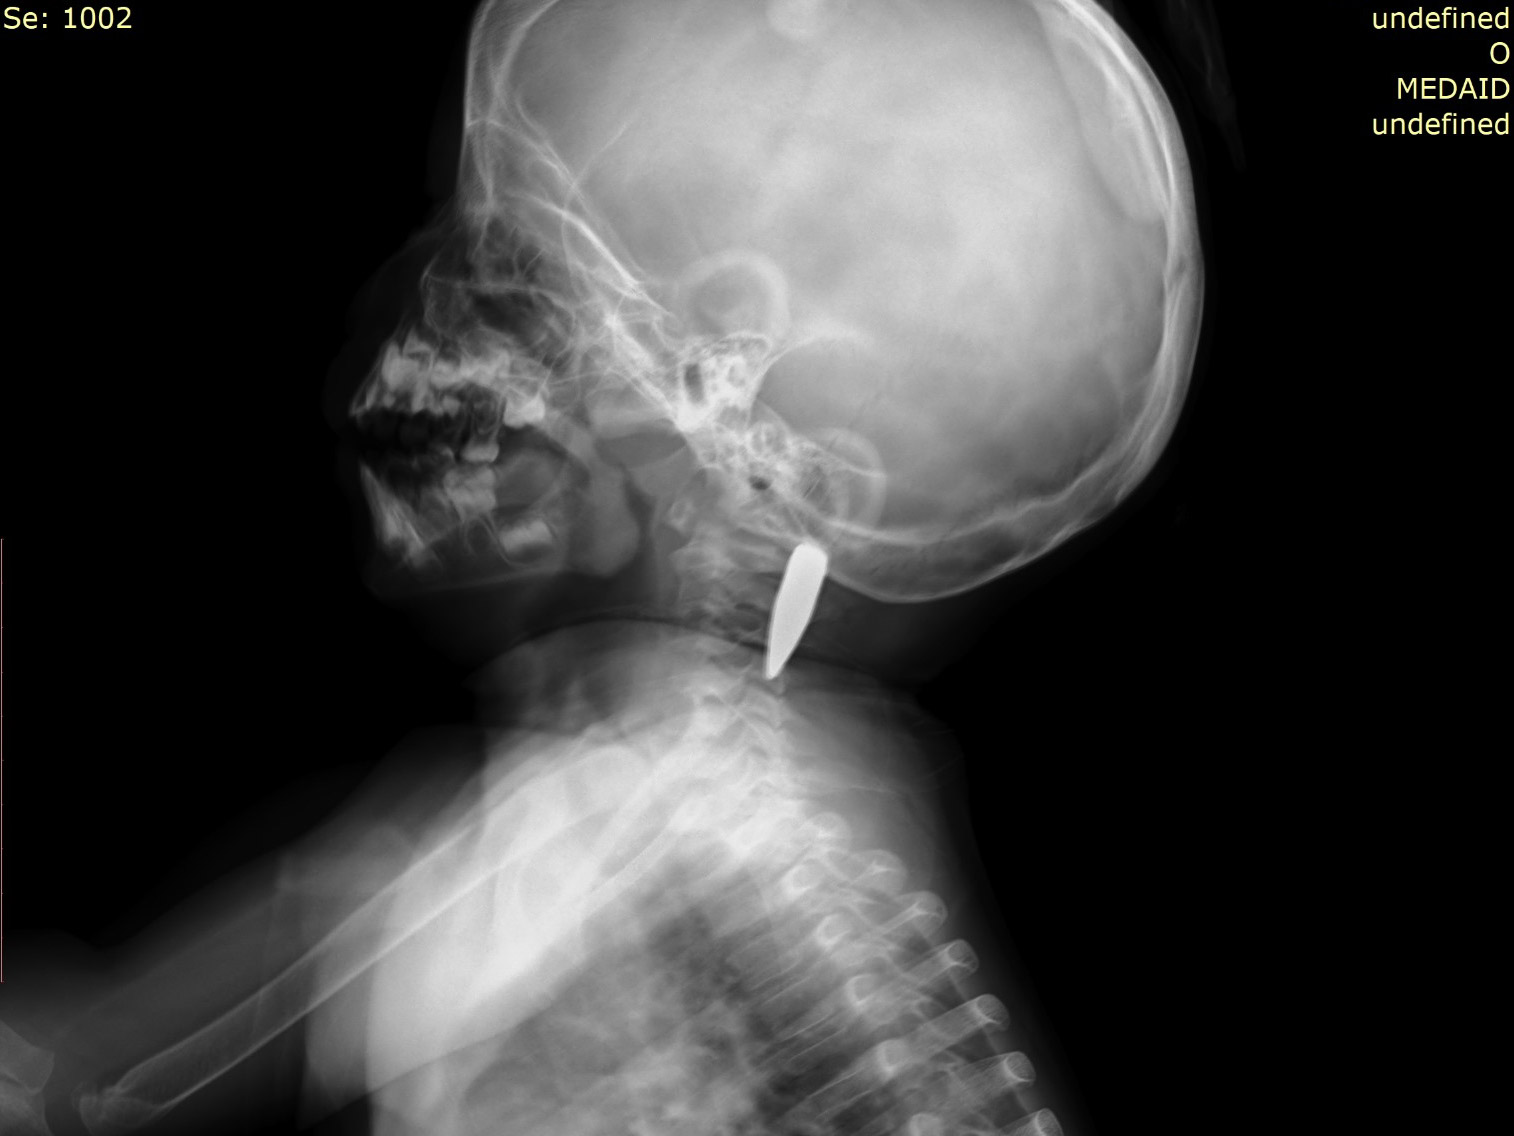

Though they thought they were safe, at 3AM on 1 September, Razan was shot in the neck. The bullet passed through makeshift walls of their tent, through the mother’s hip and into Razan’s neck, lodging itself millimetres from her spinal cord.

“The ambulance rushed her to Nasser Hospital for a CT scan and afterwards she was brought back here so that the UK-Med team could remove the bullet in the operating theatre. Razan was in surgery for nearly three hours, but when she came out of the OT, all the medical staff were overjoyed with the outcome. The surgery was a success, without any complications. I was so happy – one thousand thanks to UK-Med. They did a good thing for my child. If she’d gone to another hospital she could have died. Instead, she has been given a new life.”